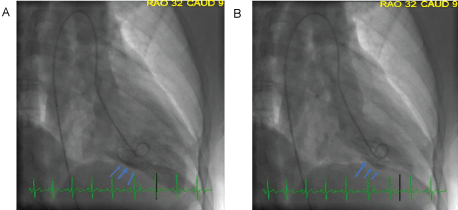

A 48-year-old woman with history of ADHD was awakened by new onset, severe chest pain which prompted her to come to the emergency department (ED). The initial heart rate was 88 and blood pressure was 147/53. There was intermittent ventricular bigeminy. Troponin I was initially undetectable and then elevated to 1.7 ng/mL six hours later, followed by a gradual decline. The initial electrocardiogram, obtained during chest pain, demonstrated normal sinus rhythm with subtle, less than 1 mm ST elevation in the inferior leads. Subsequent ECGs, obtained after chest pain ceased, showed resolution of ST segment elevation, followed by T wave inversion in the same leads”. These tracings have been added as Figure 1. Her initial echocardiogram demonstrated normal global left ventricular wall motion and normal ejection fraction. She was taken for cardiac catheterization for evaluation of NSTEMI. Cardiac catheterization revealed angiographically normal vessels (Figure 2) and mid inferior wall hypokinesis on left ventriculography (Figure 3). A spasm provocation test was not performed due to concerns about risk from induced spasm.

Figure 2: Coronary angiography of A) PDA; B) RCA showing non-obstructive coronary arteries. View Figure 2

Figure 3: Left ventriculogram in A) Diastole; B) Systole showing mid inferior wall hypokinesis. View Figure 3